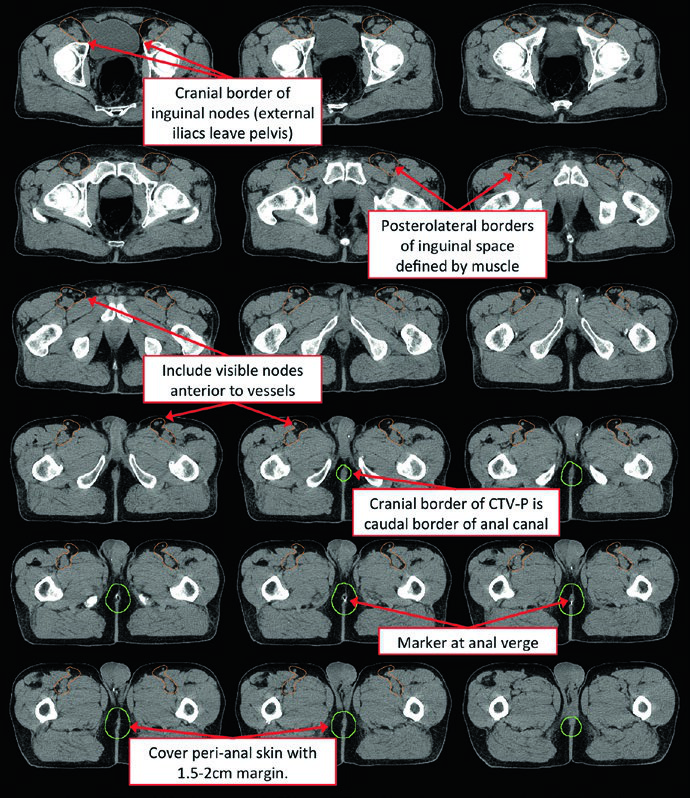

Atlas de Contorno: Regiões Nodais Eletivas

O atlas de contorno anorretal do RTOG descreve três regiões CTV que devem ser incluídas para todos os pacientes com câncer de canal anal. O Australasian GI Trials Group Atlas detalha sete regiões eletivas. Há desacordos entre as diretrizes RTOG, AGITG e BNG quanto ao contorno dos linfonodos inguinais — dados recentes mostram que 10–29% dos linfonodos inguinais envolvidos ficam fora das bordas nodais recomendadas.

| CTV-A (perirretais, pré-sacrais, ilíacos internos) | Pelve inferior: borda inferior 2 cm abaixo da doença macroscópica, incluindo mesorreto inteiro. Pelve média: reto, mesorreto, ilíacos internos, margem de 1 cm na bexiga. Pelve superior: até bifurcação das ilíacas comuns (~promontório sacral). Margem de 7–8 mm nos vasos ilíacos internos |

| CTV-B (ilíacos externos) | Fronteira entre inguinal e ilíaco externo na extensão inferior dos vasos obturadores internos (borda superior dos ramos púbicos superiores). Margem de 7–8 mm, ao menos 1 cm anteriormente |

| CTV-C (inguinais) | Extensão inferior 2 cm abaixo da junção safeno-femoral. Contornar compartimento inguinal inteiro incluindo pequenos vasos e linfonodos |

Fonte: Target Volume Delineation and Field Setup, 2nd Edition (Table 19.3 — Atlas de Contorno Anorretal RTOG)

Para cobrir adequadamente a cadeia inguinal, recomenda-se: margem radial de 2 cm ao redor dos vasos femorais, 1 cm ao redor da junção safeno-femoral e 3 cm de margem medial/lateral ao longo do ligamento inguinal inferior. A borda caudal do CTV inguinal deve estar no nível da margem anal.